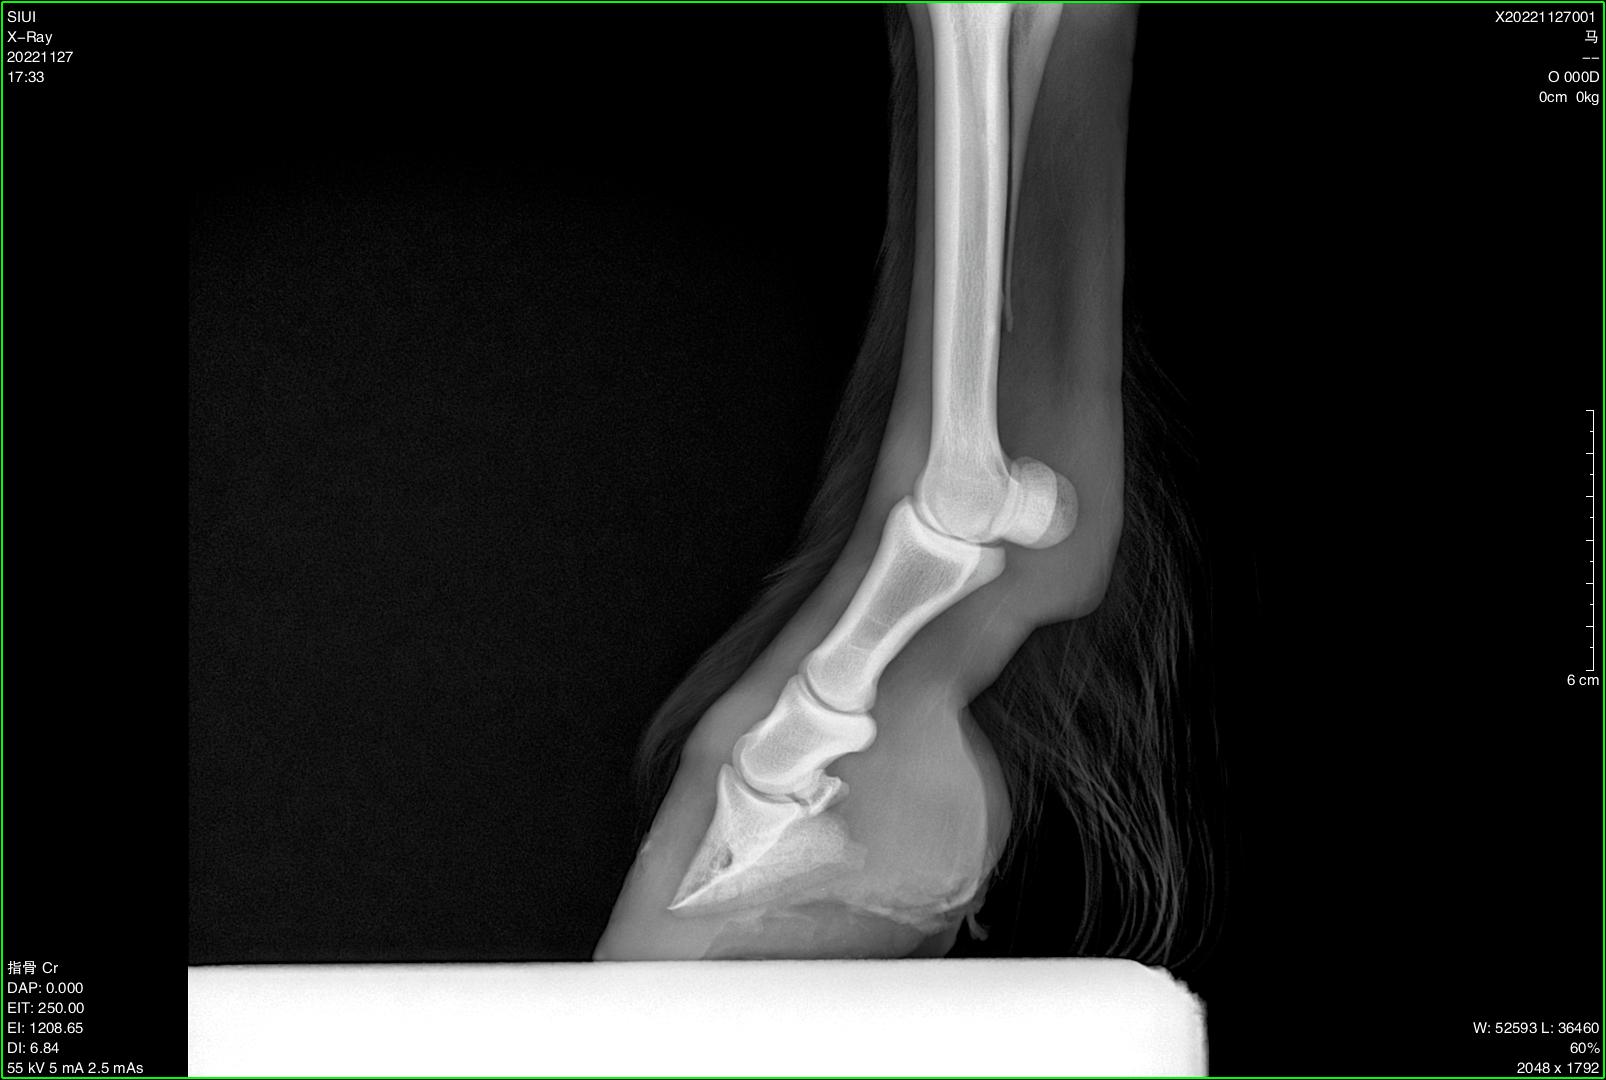

Veterinary Ultra-Portable DR System

SIUI veterinary ultra-portable DR system currently includes 2 models, SR-100 Vet and SR-300 Vet. An ultra-portable DR system consists of an ultra-lightweight X-ray generator, a wireless flat panel detector, and a user-friendly workstation.

The X-ray generators of SR-100 Vet and SR-300 Vet feature different portable designs, thereby accommodating the operational preferences of different veterinarians and adapting to diverse application environments. All-in-one backpacks, suitcases, and various types of stands are available for convenient transportation and application at stables, farms, zoos, etc.

Diverse Application Scenarios:

● Stables